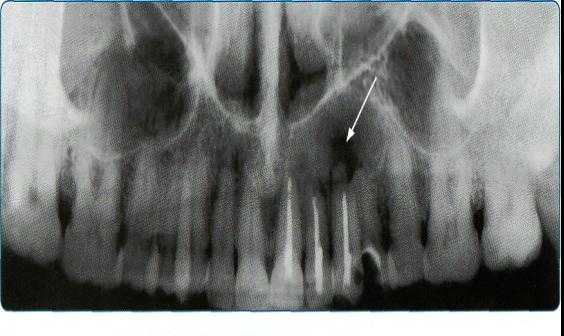

На обзорных рентгенограммах черепа определяются обе верхнечелюстные кости и нижняя челюсть, образующие костные стенки полости рта.

Прямая передняя проекция. На обзорной рентгенограмме черепа в прямой передней проекции (рис. 79) отчетливо выявляются боковые поверхности альвеолярных отростков (62в) и тел верхнечелюстных костей (62), переходящие почти под прямым углом в нижние поверхности скуловых костей (61). В телах верхнечелюстных костей прослеживаются одноименные воздухоносные пазухи (62а), а между ними срединно видна носовая полость .

Анализ верхнечелюстных костей затруднен в связи с проекционными наслоениями на них шейных позвонков.

Носо-подбородочная проекция. На обзорной рентгенограмме черепа в носо-подбородочной проекции наблюдается меньше проекционных наслоений костей черепа и лица, чем в прямой передней проекции. Однако и при этом затрудняется анализ нижних отделов верхнечелюстных костей, участвующих в образовании верхней, передней и боковых костных стенок полости рта. В этой проекции выявляются межверхнечелюстной шов и скуло-верхнечелюстные швы. Последние имеют слабую зубчатость, а межверхнечелюстной шов дает вертикаль, щелевидное просветление с ровными контурами. Иногда они ошибочно принимаются за травматические повреждения верхнечелюстных костей.

Рис. 79. Рентгенограмма черепа в передней обзорной проекции.

61 — скуловая кость; 62 — тело верхней челюсти; 62а — верхнечелюстная пазуха; 62в—альвеолярный отросток верхней челюсти; 64 — нижнеглазничный край; 69 — дно носовой полости. Нижняя челюсть: 77 — тело; 77а — основание; 776 — альвеолярная дуга; 77г — мыщелковый отросток; 77 д— венечный отросток; 77е — угол; 78а — головка.